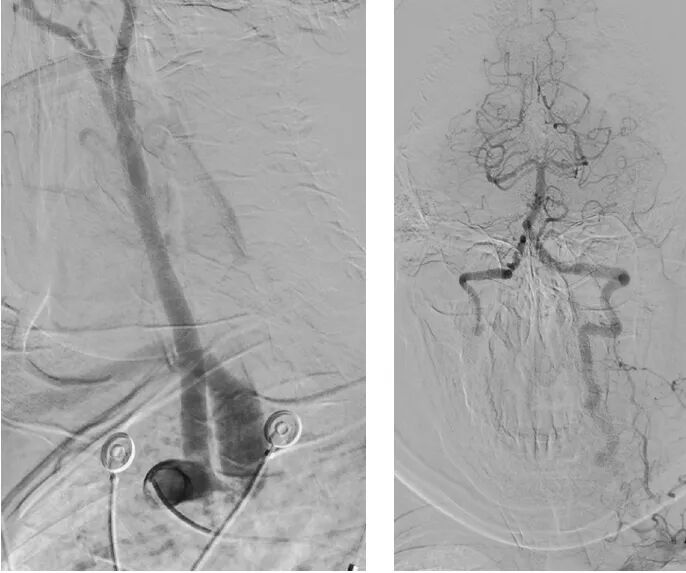

· 左侧桡动脉入路造影

明确右侧锁骨下动脉起始部重度狭窄及盗血

· 动脉鞘连接压力传感器,支架前双侧动脉压对比(左/右)

· 10-29mmOminiLink支架

▪18导丝送入18系统球囊预扩;

▪送入10-29mmOminiLink支架;

▪支架植入及植入后造影

支架覆盖理想,狭窄解除。

· 术后造影确认盗血消失,动脉压测量双侧对比(左/右)